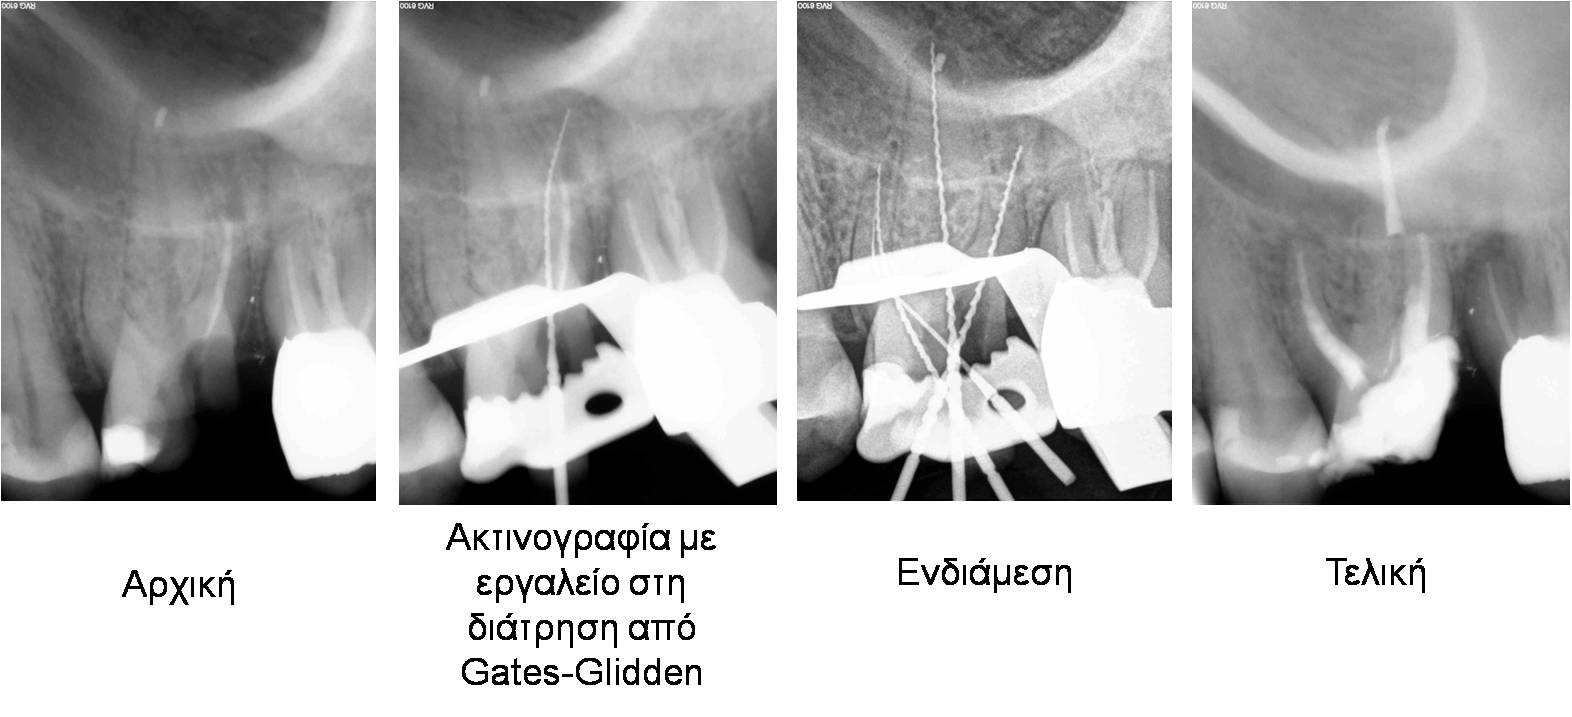

Περιστατικό 5

Αντιμετώπιση διάτρησης ρίζας